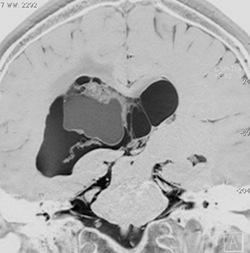

20代の男性の神経細胞腫です。側脳室の中のとても大きな腫瘍です。上段はガドリニウムという造影剤を入れた時のMRIです。下段の中央はCTですが,石灰化が見られます。脳外科の先生には,この脳室内腫瘍は一見transcallosal approach(経脳梁到達法)という手術で取れるように見えるかもしれませんが,そうではなくて,脳室の壁とくに上壁と側壁にくっついているのでなかなか取れません。この患者さんの場合は右の頭頂葉というところからtranscortical approach(経皮質到達法)で全摘出しました。後遺症もなく再発もなく術後10年が過ぎています。全部とれれば治ってしまう腫瘍です。